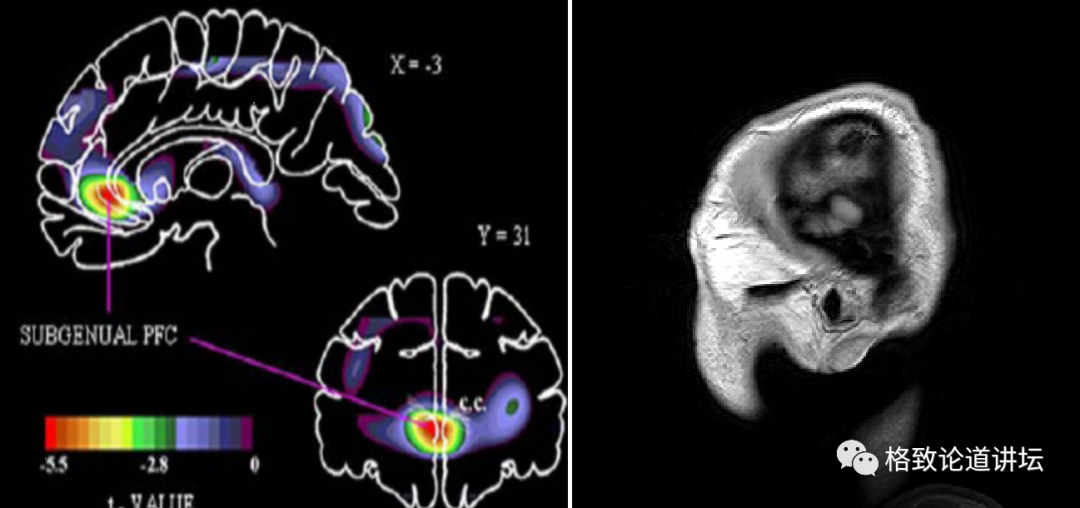

那么有没有可能在人脑上直接研究?大家知道现在医学家、神经科学家、工程学家和物理学家,已经发明出了越来越精密的脑影像技术,我们已经可以非常清楚地看到抑郁症的人脑,哪些脑区发生了变化。

例如额叶,前额叶,杏仁核,缰核,下丘脑,能看到这些部位的结构发生了变化,但是它无法看到分子层面,无法看到具体的化合物改变。